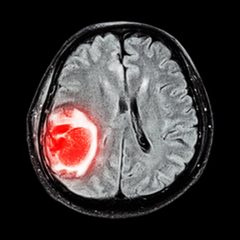

Диагностика опухоли мозга в Израиле осуществляется с применением самого современного оборудования и новейших методик исследования. Для стопроцентного подтверждения диагноза больницы Израиля используют целый комплекс исследований:

- Компьютерная томография;

- МРТ;

В большинстве случаев для получения достоверного диагноза достаточно результатов магнитно-резонансной терапии и компьютерной томографии. Дополнительные обследования назначаются на усмотрение лечащего врача. Компания Tlv.Hospital сотрудничает с самыми прогрессивными медицинскими учреждениями в Израиле. Мы готовы организовать для вас лечение в Израиле на высшем уровне.